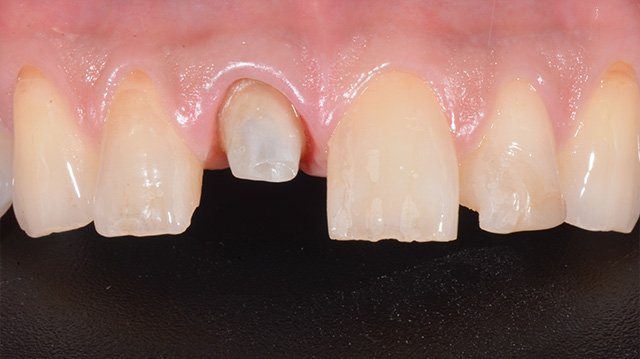

| 年代・性別 | 50代 男性 |

|---|---|

| 主訴 | 前歯を綺麗にしたい |

| 治療回数 | 3回 |

| 治療期間 | 約1ヶ月 |

| 費用 | 仮歯 5,500円 ジルコニアクラウン 176,000円 |